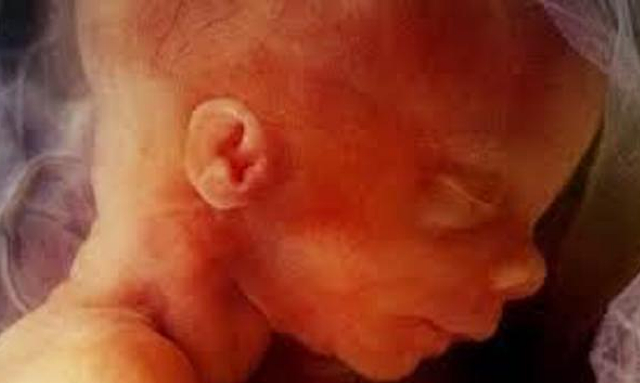

El embrión mide aproximadamente 13 mm desde la punta de la cabeza hasta las nalgas.Comienza en su cabeza a formarse y perfilarse las orejas , los ojos y donde empieza a formarse la punta de la nariz, la cabeza es todavía muy grande en comparación con el resto del cuerpo. Por eso, aunque su columna vaya enderezándose poco a poco, la cabeza todavía permanece hacia delante. También comienza a borrarse la columna del embrión y comienza a formarse los cuatro huesos unidos los cuales forman el coxis.

• Semana 9

Semana 9

En la 9 semana del embarazo tu bebé,que en este momento se conoce como feto, ahora que la cola del embrión ha desaparecido,en esta semana ya comienza a estirarse y enderezar su tronco y este bebe mide cerca de 2,5cm de largo.